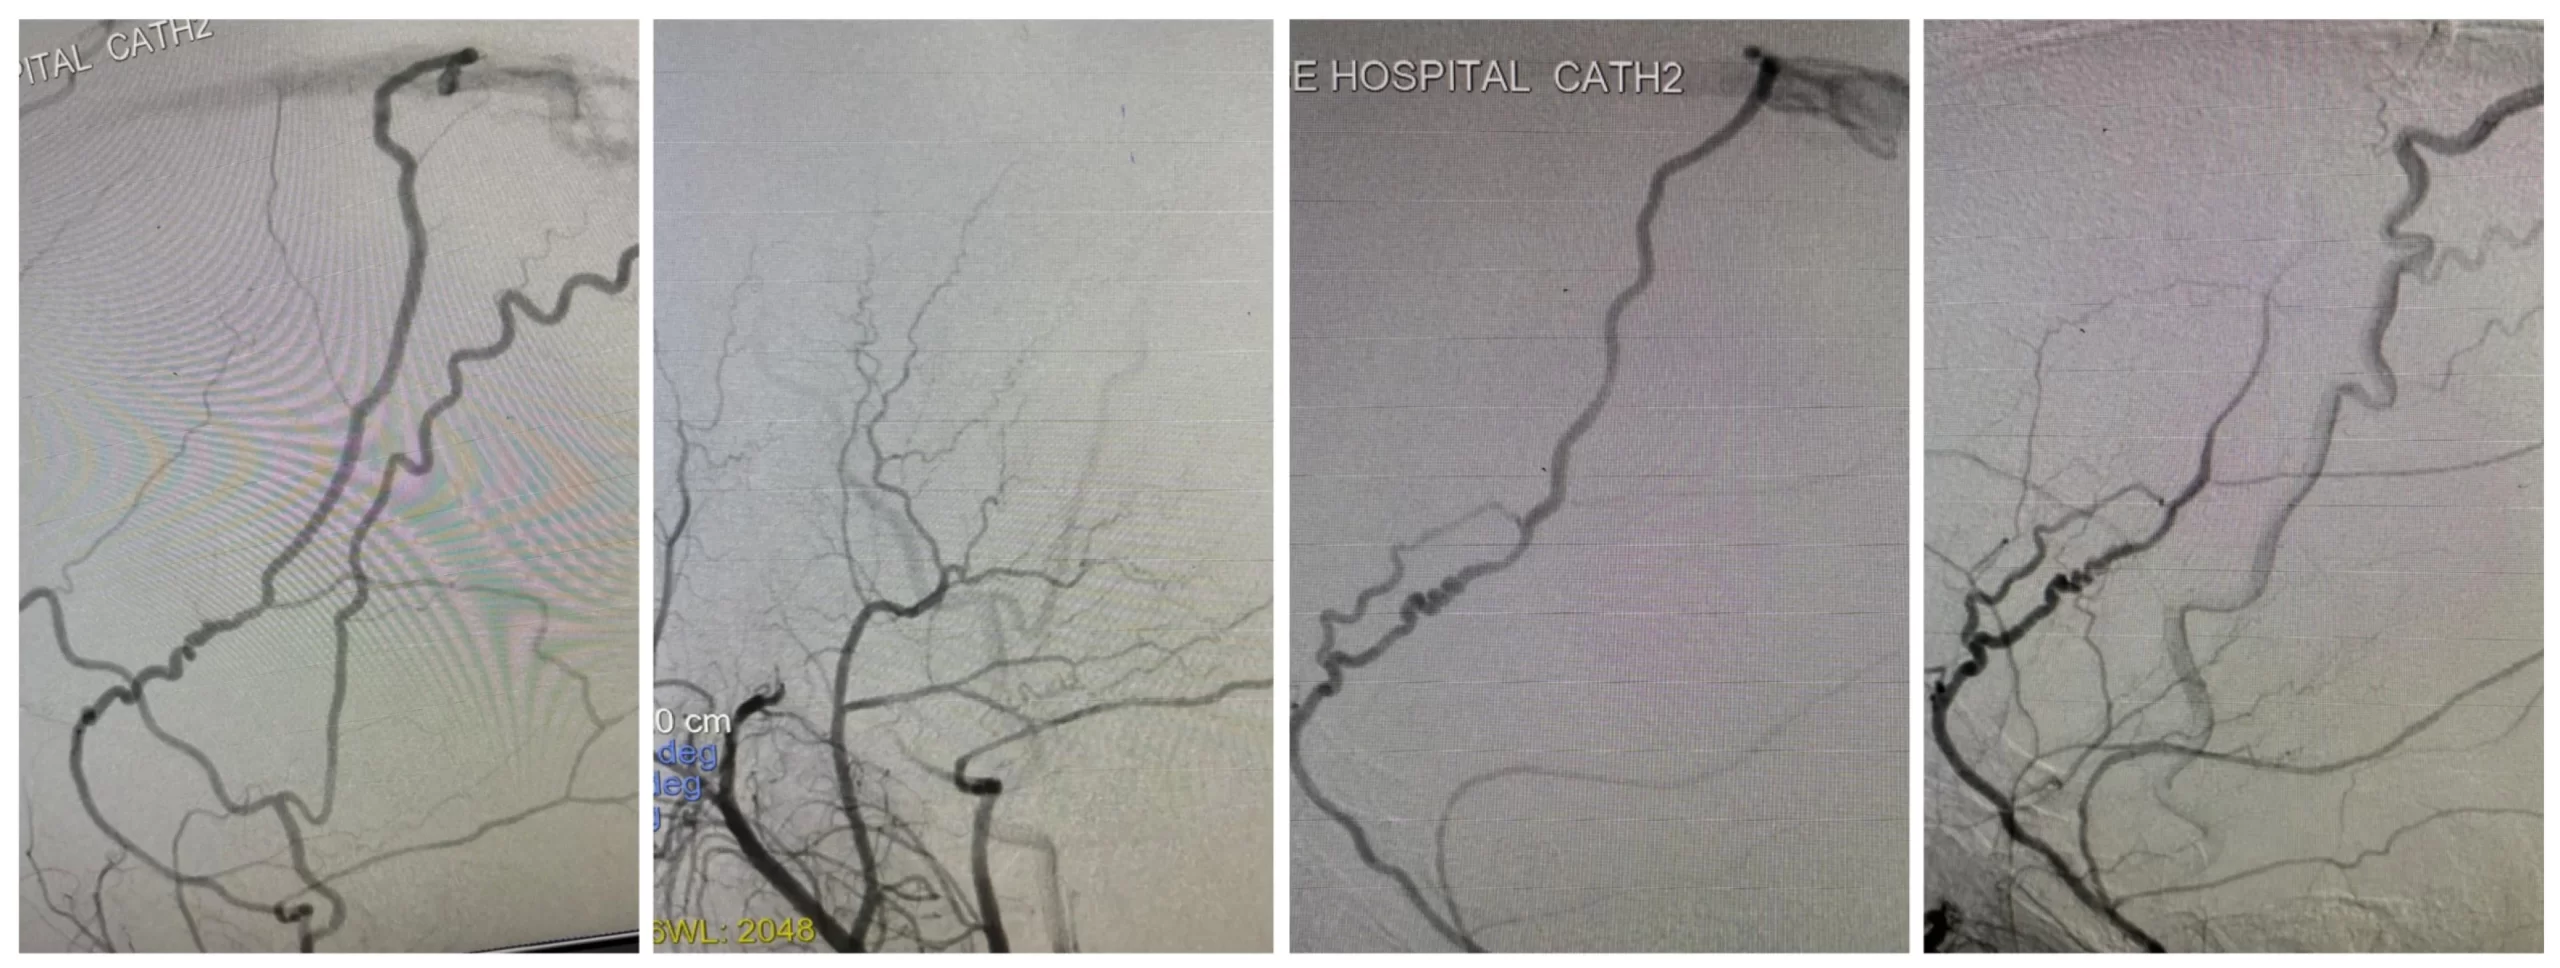

43 year old gentleman with history of previous CVST and now ongoing recurrent severe headaches was evaluated with MRI and cerebral DSA which showed bilateral Cognard type II a+b dural AV fistula at the superior sagital sinus fed by anterior MMA.

After super selective angiograms, both MMA feeders showed multiple tight loops. On the left the microwire straightened the loops and Asahi parkway went close to the fistula. On the right it wouldn’t negotiate a mid proximal very acute loop. I went on to embolize both sides with glue achieving complete obliteration.